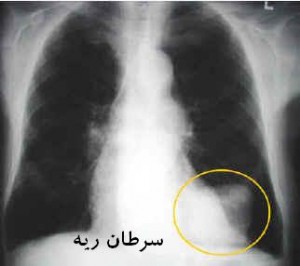

سرطان ریه، از آن دسته بیماری است که بر خلاف تصورات مردم، اگر به زودی تشخیص داده شود، قابل درمان است.

به گزارش روزنامه خراسان، سرطان ریه سالانه قربانیان زیادی میگیرد؛ بیشتر مردم ابتلا به این بیماری را در حکم مرگ میدانند؛ در صورتی که اگر این بیماری زود تشخیص داده شود قابل درمان است؛ از جمله علایمی که ممکن است نشان دهنده ابتلا به سرطان ریه باشد، به شرح زیر است: